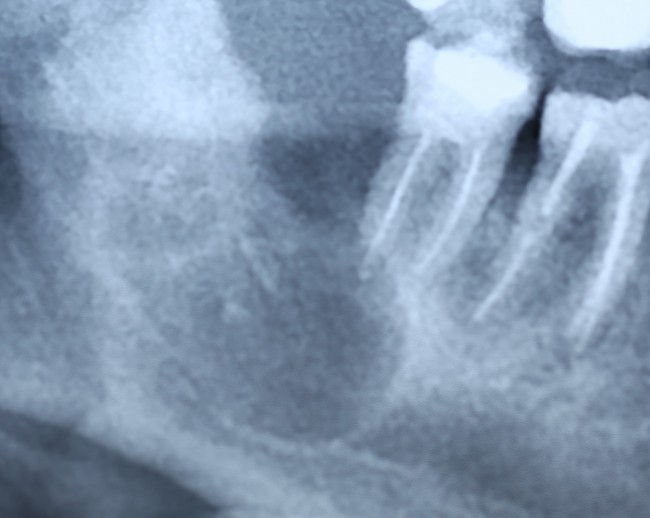

Давайте еще раз посмотрим на снимок:

Что мы на нем видим? Ну да, есть два лишних зуба.

К сожалению, мы не можем по ортопантомограмме…

- … достоверно определить положение зубов. Ортопантомограмма искажает.

- …определить их отношение к нижнечелюстному каналу и соседним зубам. Они находятся ближе к щеке или языку? Нижнечелюстной канал проходит за, между или перед ними? Мы должны ОБЯЗАТЕЛЬНО знать ответы на эти вопросы.

- … самое главное — спланировать операцию в целом и схему операционного доступа, в частности! Это важно? Еще как!

Что, собственно, мы и делаем:

По-моему, на скриншоте всё понятно. Зубы, которые нужно удалить нафиг, обозначены белой стрелкой и словосочетанием «удалить нафиг!«. Темным пунктиром обозначены контуры зубов. Черная точка — просвет нижнечелюстного канала. Снизу слева я попытался наглядно показать схему взаимного расположения и отношения сверхкомплектных зубов к нижнечелюстному каналу. Ну и, внимательно изучив КТ, я принял решение, что операционный доступ нужно делать с язычной стороны.